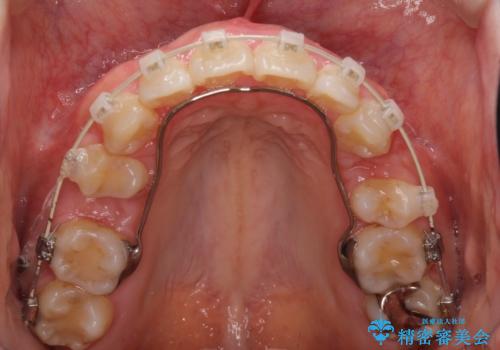

上下左右の歯を1本ずつ、合計4本抜歯してワイヤーにて矯正治療をすることとなりました。

前から4番目の歯を抜歯することが多いのですが、右上の前から5番目の歯が神経の治療済みであり、こちらの歯を抜歯する計画としました。

通常より治療期間を要しましたが、健康な歯を残すことができました。